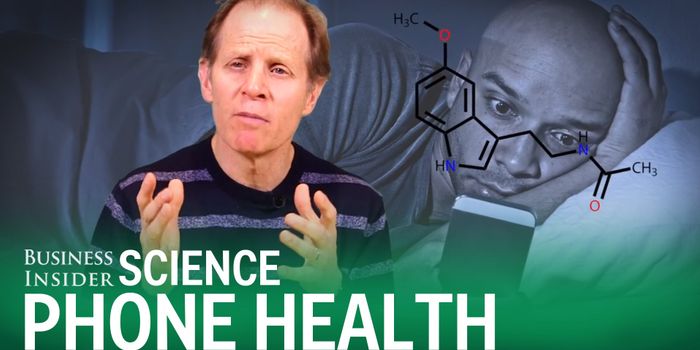

JAN 30, 2019TechnologyLots of people spend more time staring at digital screens than they should. Significant amounts of the population work o ...

DEC 27, 2017InfographicsDigital screens are quickly becoming integrated into all aspects of our daily lives. The average American spends 11 hour ...